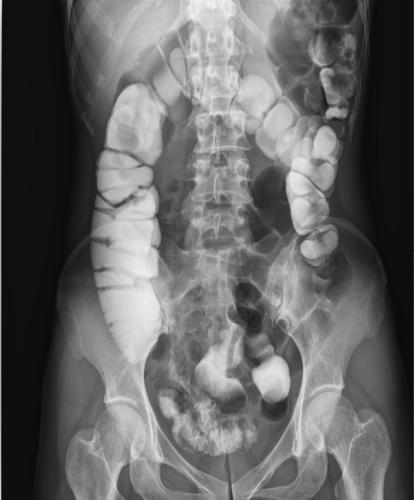

其次,數(shù)字化成像極大地提高了圖像的清晰度、對比度、分辨率,與傳統(tǒng)的胃腸機相比,空間分辨率可提高一到兩倍,圖像質(zhì)量明顯提升。還具有視頻保存回放功能,檢查結(jié)束后,仍可通過視頻回放對病人進(jìn)行診斷,不需要重復(fù)檢查。由于胃腸道疾病的癥狀大同小異,缺乏特征性,特別是一些早期無癥狀的疾病如早期胃癌或較小的病變在其中受益匪淺。動態(tài)DRF胃腸道造影高清圖像

動態(tài)DRF胃腸道造影高清圖像